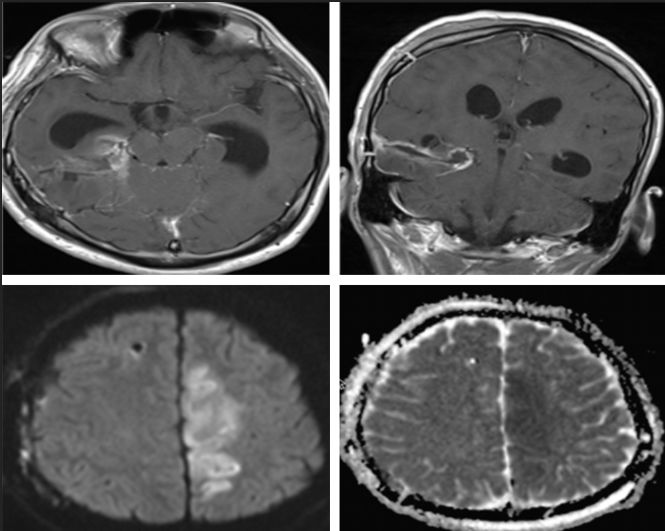

术后2周余复查头颅CT:

脑室系统扩大及,侧脑室旁白质间质性水肿(图6)。

图6.术后2周头颅CT:脑室系统积水及颅内高压进行性发展。